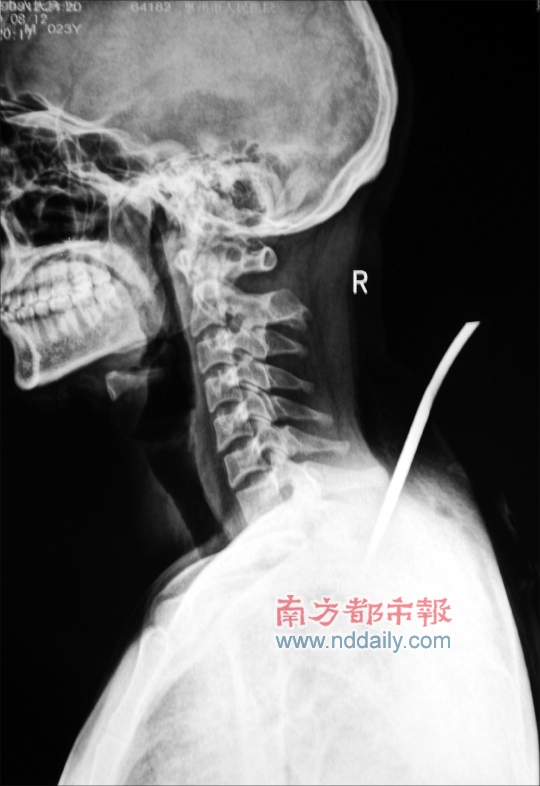

X光照清晰地显示,患者肩部被插入一把15厘米的刀。记者田飞 通讯员 黄宇强 摄

来自贵州的戴先生,在宾馆与女网友会面时,遭遇3名陌生男子袭击,身中6刀伤及胸腔,目前仍在惠州市第三人民医院(原惠州市人民医院)抢救。

发现客人受伤后,宾馆工作人员报警,当地派出所民警很快赶到,戴先生被送往惠州市第三人民医院急救。经诊断,戴先生伤情严重,背部最重一刀伤及胸腔,并且刀断在体内。经紧急手术,目前戴先生已脱离生命危险。戴先生称在惠州从未与人结怨,和女网友也是第一次见面,怀疑袭击他的人是女网友的前男友,戴先生的说法并未得到证实。目前,案件仍在进一步调查中。